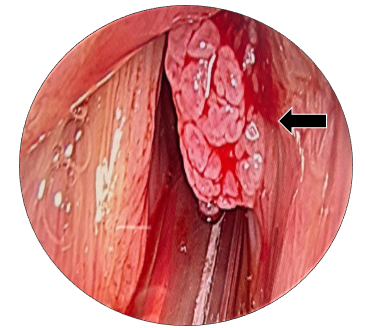

On examination he was sitting well with normal blood pressure. His SpO2 was 99% without any support. Oral cavity examination was normal. Rigid laryngocopy revealed a papillomatous pinkish swelling presented over anterior 2/3rd surface of right true vocal fold. This lesion reaches till anterior commissure and involving the anterior 1/3rd aspect of left true vocal fold.(Figure 1A-C) Both the true vocal folds were mobile with normal rest of the anatomical subsites. Patient underwent for computed tomography (CT) scan and it was reported as 8.3 x 8.8 x 7.1 mm nodular mildly enhancing soft tissue noted at anterior part of the right true vocal cord. (Figure 2) The patient was scheduled for microlaryngeal surgery under general anaesthesia.

Figure 1 (A to C) Laryngoscopic view of true vocal folds, showing papillomatous lesion over anterior 2/3rd true vocal fold, involving anterior commissure and left anterior1/3rd true vocal fold. bilateral true vocal folds were mobile.